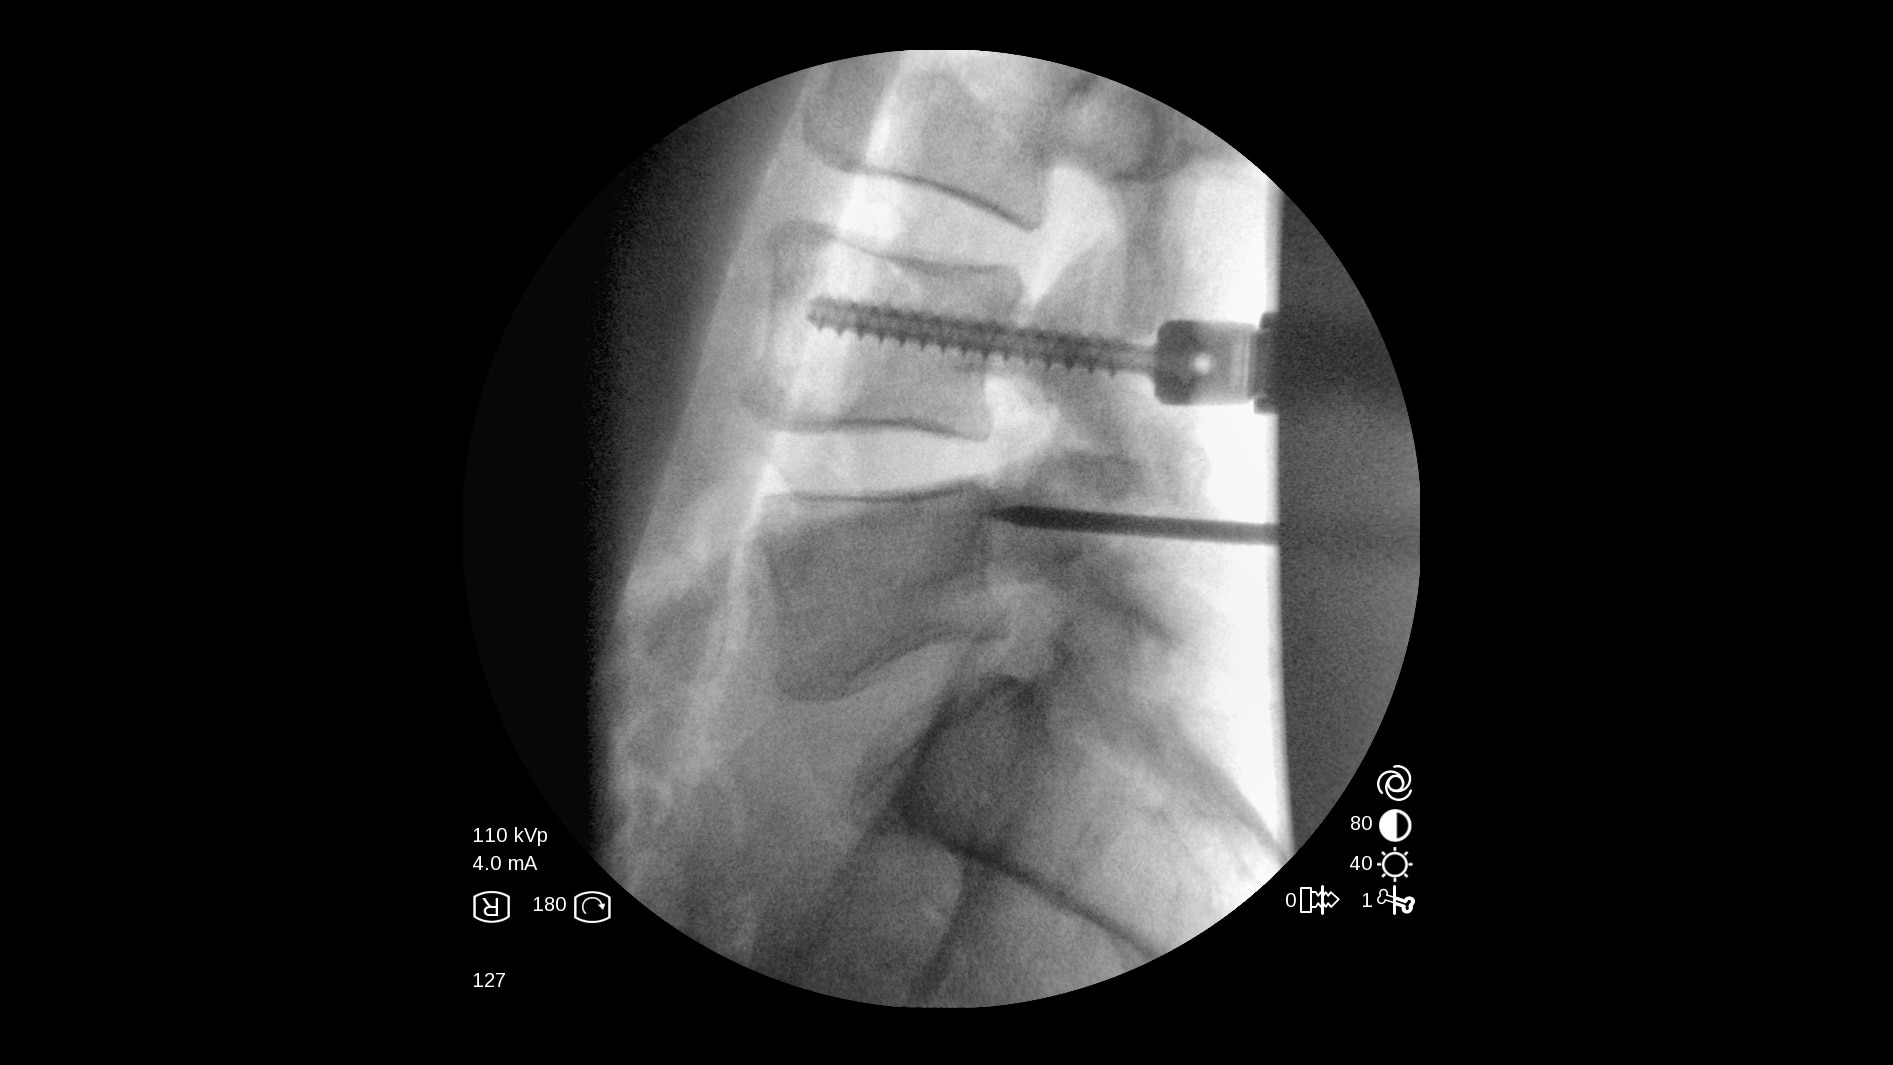

All-in-one mobile C-arm

The OEC One all-in-one mobile C-arm offers superb imaging capabilities, made more accessible for a variety of procedures — from pain management to peripheral vascular. Enjoy image processing advancements in clear, detailed images.

Get the images you need without adjusting system settings from the first shot to the last shot with OEC image processing software.

OEC One utilizes automatic intelligence software to sense anatomy and provide high quality imaging at optimal mA and kV levels, even when anatomy is not properly centered in the field of view.